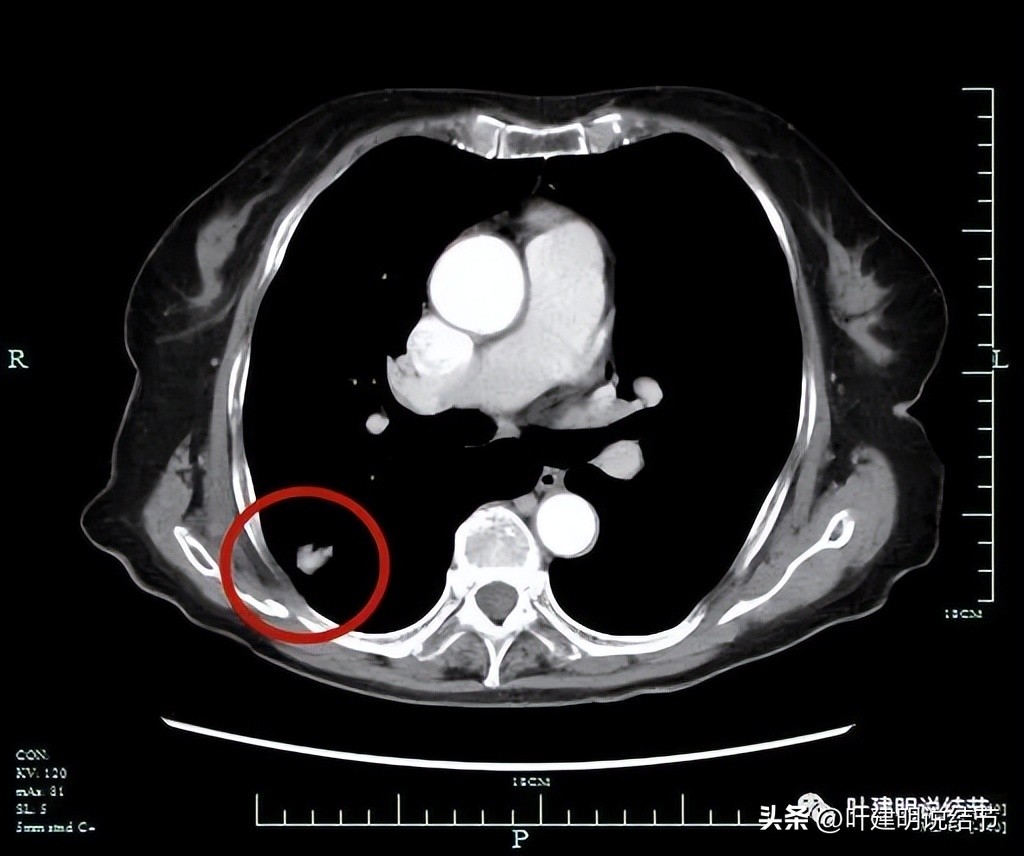

腔静脉旁有肿大淋巴结(黄色箭头)。

上图是PET-CT怀疑转移的淋巴结,跨在肺动脉上(跨在尖前干的上方)

PET说右上后段考虑恶性病变。右肺门区,即上述说肺动脉上方的淋巴结是考虑转移可能性大,但没有说纵隔内的淋巴结有异常高摄取。还是就是左侧髂骨内结节样不均匀稍高密度影,葡萄糖代谢增高,要考虑良性肿瘤或肿瘤样病变可能性大。

上图是所谓考虑转移可能的淋巴结。